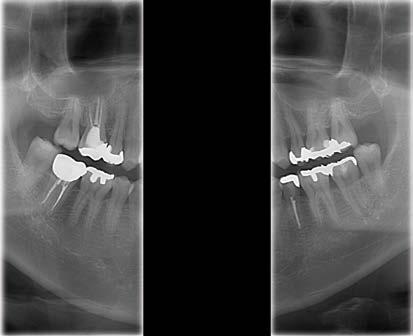

Implantologie

Der Patient stellte sich nach dem Einsetzen eines Implantats im Bereich des lateralen Schneidezahns oben links zu einer routinemäßigen Nachuntersuchung vor. Das Implantat war 3 Monate zuvor eingesetzt worden. Auf koronaler, sagittaler und axialer Ebene war ein großer, runder, gut definierter, glatter Bereich mit geringer Dichte im Zusammenhang mit der apikalen Ansicht des Implantats zu erkennen. Die hochauflösenden Bilder zeigen, dass die bukkale Kortikalis fehlt und bestätigen daher die schlechte Prognose aufgrund der vorhandenen Periimplantitis.